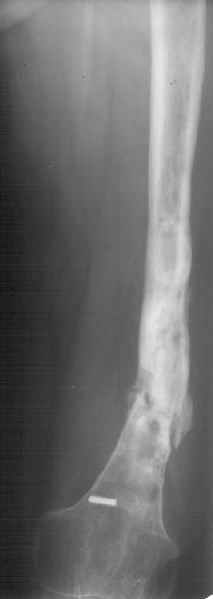

К нам поступила худощавая женщина 48 лет, которой года 2,5 назад был выполнен остеосинтез бедра пластинкой в одной из горбольниц. В сентябре 2001 г. пластинку убрали. Начала разрабатывать движения, ходила с тростью. С января этого года

отмечает усугубление деформации бедра и улучшение движений "в коленном суставе". При осмотре имеетсяподвижность на месте перелома (псевдартроза), больше в сагиттальной плоскости. Рентгенограммы в приложении(фас; профиль). Полностью угол, открытый кзади, под нагрузкой не устраняется. "Сгибается" еще градусов на 30. Ходит с тростью. Надколенник неподвижен, в суставе, видимо, движений нет совсем. В любом случае надо, видимо, начинать с восстановления оси и стабилизации бедра. Как окончательный фиксатор хотелось бы использовать интрамедуллярный стержень. Можно ли в данном случае устранить угол одномоментно? Или лучше дозированно? Нужна ли костная пластика местно? Не стоит ли пойти на мобилизующую операцию в один этап? Если да, то какую?Может быть, есть еще какие-то моменты, которые следует учесть?Спасибо заранее.-- Best regards, Alexander N. Chelnokov

The pt has 20 degree of varus and 30-40 degree of procurvatum Acute correction may compromise the nurovascualr structures. Moreover xray shows evidence of infection and she has almost knee range of motion.

In such a case I would suggest a gradual correction with an ILIZAROV frame as an oblique plane defoemity.

Не сформировалось у нас убежденности в целесообразности мобилизующей операции в один этап с остеосинтезом. Решили пойти по максимально щадящему пути. Первым этапом наложили аппарат. Снимок (см. приложение) сделан в положении максимально возможной коррекции оси, достигаемой одномоментно исправлением "об коленку" с ручным растягиванием колец сзади. Варус удалось убрать, а вот антекурвацию, от греха, лучше устраним дозированно, дней за 7-10. Потом планируем антеградный закрытый интрамедуллярный остесинтез. Буду признателен за отклик.